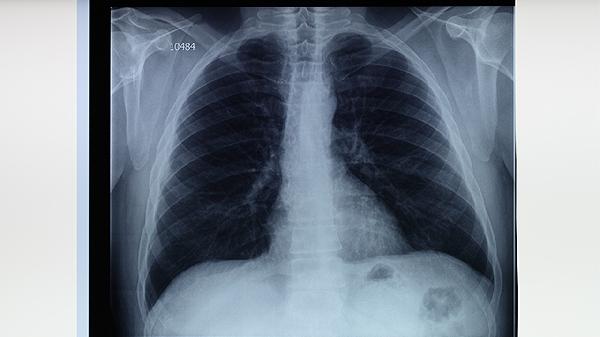

胸部X線能直觀顯示肺結核引起的肺部病變特征,如上葉尖后段或下葉背段的浸潤影、空洞形成等典型表現(xiàn)。該檢查對診斷活動性肺結核具有重要價值,但需注意與其他肺部疾病鑒別。對于疑似病例,建議同時進行痰液檢查以提高診斷準確性。